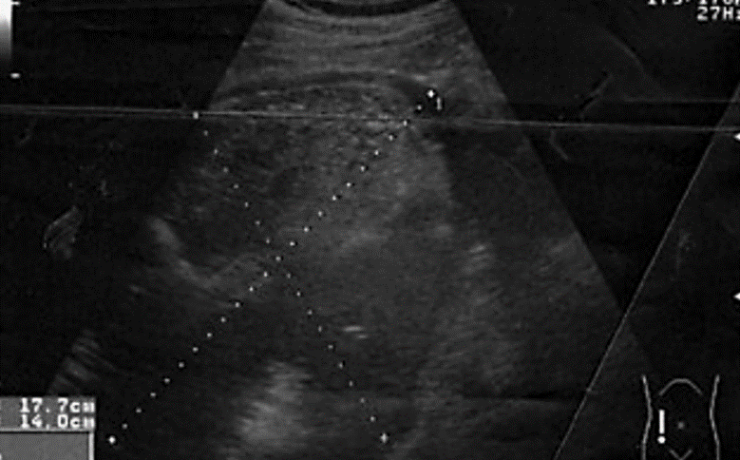

La vesícula biliar es una bolsa de 7 a 10cm de longitud y de 3 a 5 cm de ancho, la cual mantiene en promedio un volumen de 30-50ml; tiene forma piriforme (forma de pera), la cual se divide para su estudio en tres secciones: el fondo, el cuerpo y